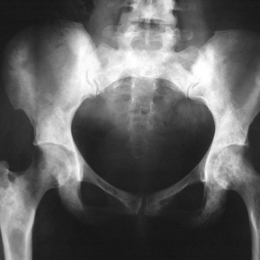

Radiographic imaging is used to help form a diagnosis. These include X-Ray, MRI, CT and Bone Scans

An example of a X-Ray is shown.